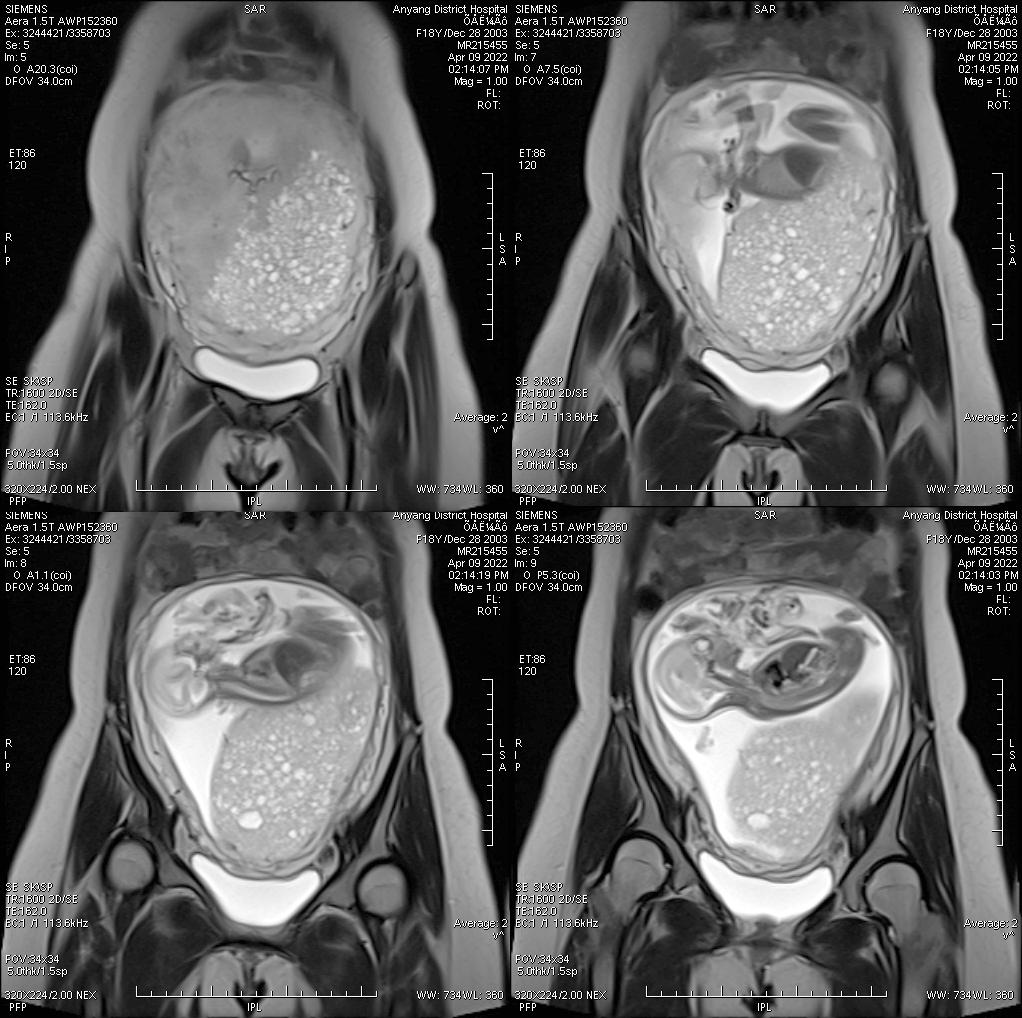

病例二

女,30 岁,侵蚀性葡萄胎,穿透宫壁全层。引道出血 20 多天,既往有 3 次人工流产病史。

侵蚀性葡萄胎

侵蚀性葡萄胎 指葡萄胎组织侵入子宫肌层局部,少数转移至子宫外,因具恶性肿瘤行为而命名。 侵蚀性葡萄胎来自良性葡萄胎,多数在葡萄胎清除后 6 个月内发生,其绒毛可侵入子宫肌层或血管或两者皆有,起初为局部蔓延,水泡样组织侵入肌层深部,有时完全穿透子宫壁,并扩展进入阔韧带或腹腔,半数病例随血运转移至远处,主要部位是肺和阴道。

组织学分为 3 型:1 型:肉眼见大量水泡,形态似葡萄胎,但已侵入子宫肌层或血窦,很少出血坏死;2 型:肉眼见少量或中等量水泡,滋养细胞中度增生,部分细胞分化不良,组织有出血坏死;3 型:肿瘤几乎全部为坏死组织和血块,肉眼仔细观察才能见到少数水泡,个别仅在显微镜下找到残存肿大的绒毛,滋养细胞高度增生并分化不良,形态上极似绒癌。

临床主要症状为阴道不规则流血,若肿瘤组织穿破子宫,则表现为腹痛及腹腔内出血症状,有时可触及宫旁转移性肿块。